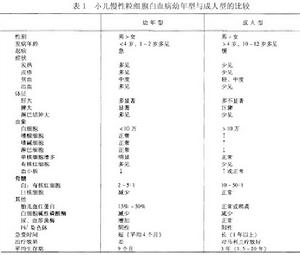

成人型慢性粒細胞白血病——表1

成人型慢性粒細胞白血病——表1中國通常採用的診斷標準歸納如下:

(2)加速期:幼年型與成人型的差別,見表1